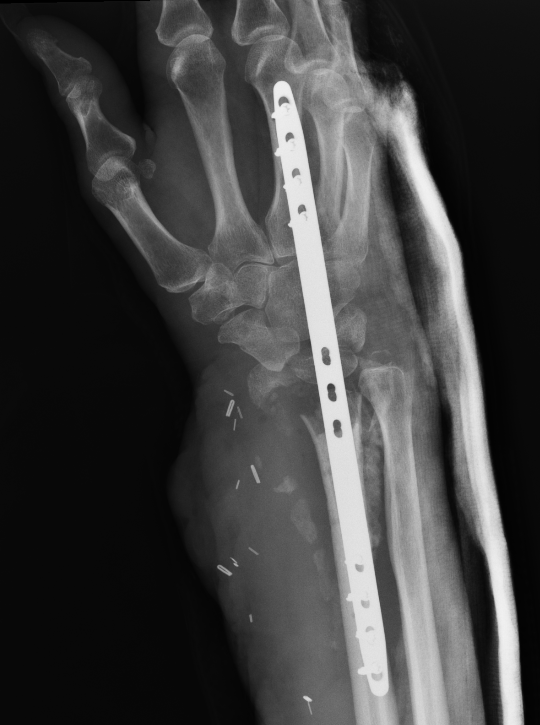

Undisplaced wrist fracture

- interrupts blood supply at a watershed area

- between 3 weeks and 3 months post injry